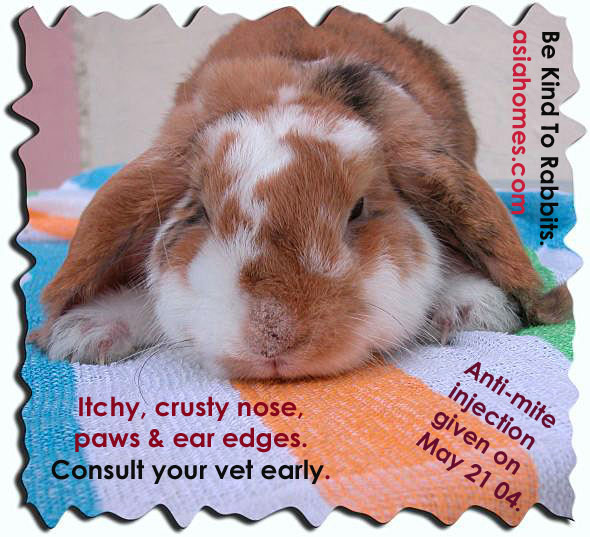

catdandruffclinic cat mange feline scabies all you need to Cat Mange is a skin disease caused by various tiny mite species Some of the causative mange mites are normal residents of your cat s skin and hair follicles while others are considered parasites Notoedric Mange In Humans best cat art Cat CareCat hair loss is not that uncommon and can be caused by many different ailments and problems Your veterinarian is the best person from whom to obtain advice diagnosis and treatment vetstreet why does my cat scratch her earsEar scratching is one of the more common reasons cats see veterinarians When the head starts shaking and claws start digging it s a safe bet that a cat has itchy ears But the cause is not always clear

Can People Get Mange, image source: www.monvt.eu

Symptoms & Treatment - Cat World, image source: www.cat-world.com.au

Symptoms, image source: www.anewbandaday.com

Treatment, image source: petsbestrx.com

Räude bei Hunden › Hunde-Info.de, image source: www.asiahomes.com